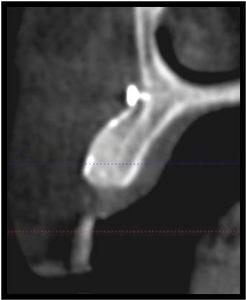

This CT scan shows the amount of bone that can be gained using bone grafting procedures.

Before